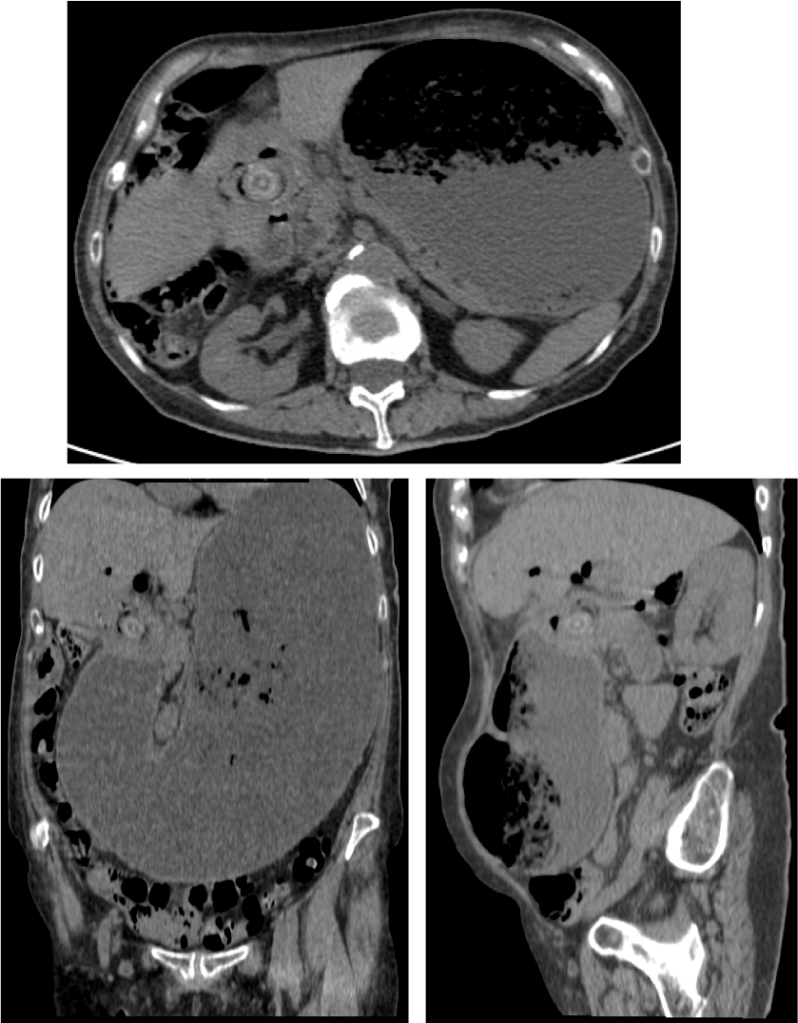

Correlacion con las imagenes anteriores

Correlacion con las imagenes anteriores: en los cortes axial, sagital y coronal puede confirmarse la diltaicón de la cámara gástrica la cual es debido a un litiasis enclavada en primera porción duodenal/píloro gástrico.

Se realiza una TC con contraste en fase portal con cortes de 3 mm y cortes finos para realizar reconstrucciones. Puede realizarse sin contraste para poner aun más de manifiesto la litiasis cálcica. La información obtenida por TC nos permite un diagnóstico rápido y preciso, además de ser una ayuda muy preciada para el cirujano a la hora de decidir el tratamiento a realizar.

Hallazgos:

• Triada de Rigler: obstrucción intestinal + neumobilia +  litiasis ectópica (solo se detecta en el 77% de los casos).

• Dilatación por obstrucción intestinal.

• Distensión de la cámara gástrica.

• Fistulas (normalmente entre vesícula y duodeno)

• Hay que tener cuidado ya que muchas litiasis no están calcificadas y su densidad puede ser similar al contenido del intestino. Pueden ser multiples, por tanto hay que poner atención para que no pasen desapercibidas y evitar las recidivas.